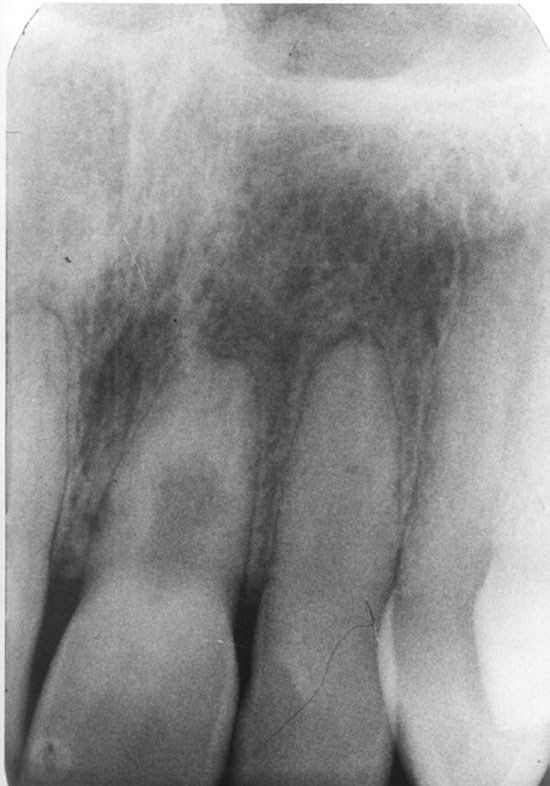

Description: Foreshortening occurs when the central ray from the tubehead is too high, making the vertical beam angulation too steep. The image appears shortened particularly at the portions of the teeth that were closest to the beam (Figure 4).

Differential Diagnosis: Visible shortening of the teeth, with somewhat wider appearance of objects closest to the x-ray head. The incisal or cuspal edge may be partially missing. The posterior teeth may show a greater distance between the buccal and lingual cusps (Figure 5).

Figure 4. Foreshortening.

Figure 4

Figure 5. Example showing distance between cusps.

Figure 5